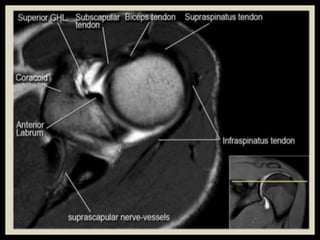

• 71.

• 85.

• 120.